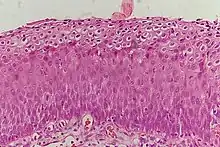

Historically, abnormal changes of cervical epithelial cells were described as mild, moderate, or severe epithelial dysplasia. In 1988 the National Cancer Institute developed "The Bethesda System for Reporting Cervical/Vaginal Cytologic Diagnoses".[12] This system provides a uniform way to describe abnormal epithelial cells and determine specimen quality, thus providing clear guidance for clinical management. These abnormalities were classified as squamous or glandular and then further classified by the stage of dysplasia: atypical cells, mild, moderate, severe, and carcinoma.[13]

CIN is classified in grades:[14]

Histology Grade | Corresponding Cytology | Description | Image |

---|---|---|---|

CIN 1 (Grade I) | Low-grade squamous intraepithelial lesion (LSIL) |

|

CIN 2/3 | High-grade squamous intraepithelial lesion (HSIL) |

CIN 2 (Grade II) |

CIN 3 (Grade III) |